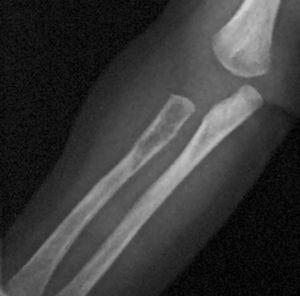

Ya en dicha unidad, con 2 meses de vida, el estudio realizado (ecografía abdominal, TC de cráneo, de región mastoidea y de tórax, así como biopsia de médula ósea) sigue sin evidenciar afectación sistémica hasta que al repetir una segunda serie ósea se descubre una lesión osteolítica en radio (fig. 1), la cual junto con la aparición de hipoproteinemia (2 g/dl), hizo considerar el grado de afectación sistémica tributario de iniciar tratamiento con quimioterapia (prednisona, vinblastina y metotrexato). Con ésta, la evolución clínica inicial es favorable, desapareciendo las lesiones cutáneas, cediendo la irritabilidad, tolerando la alimentación y ganando peso. Transcurridos casi 4 meses con tratamiento, fallece por afectación intercurrente aguda bronconeumónica no filiada (la familia no concedió la necropsia).

Figura 1. Lesión osteolítica en radio.